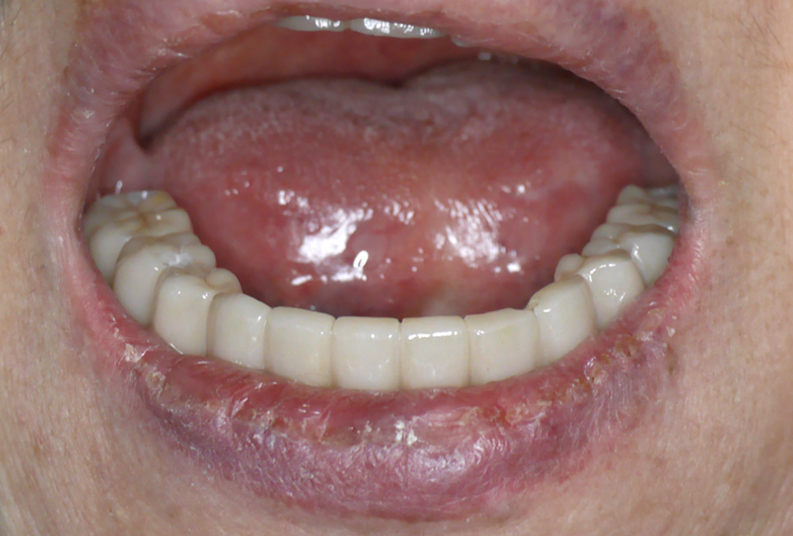

即刻安裝臨時固定假牙: 利用先進的CAD/CAM技術或預成連接件,在植體植入當天,立刻為張阿姨裝上一副堅固耐用的臨時固定假牙。這意味著張阿姨在離開診所時,嘴裡已經擁有了一副可以馬上使用的固定牙齒!

最大的驚喜是,張阿姨當天回家就能用新的臨時固定牙吃軟食了! 說話清晰,面容自然,日常生活完全不受影響,告別了鬆脫假牙的尷尬。

臨時固定假牙讓張阿姨舒適地度過了約3個月的骨整合期(人工牙根與骨頭緊密結合的關鍵時期)。3個月後,骨頭癒合穩固,張阿姨回診,醫療團隊為她取下臨時假牙,換上量身定制、更美觀、更堅固耐用的正式固定假牙。